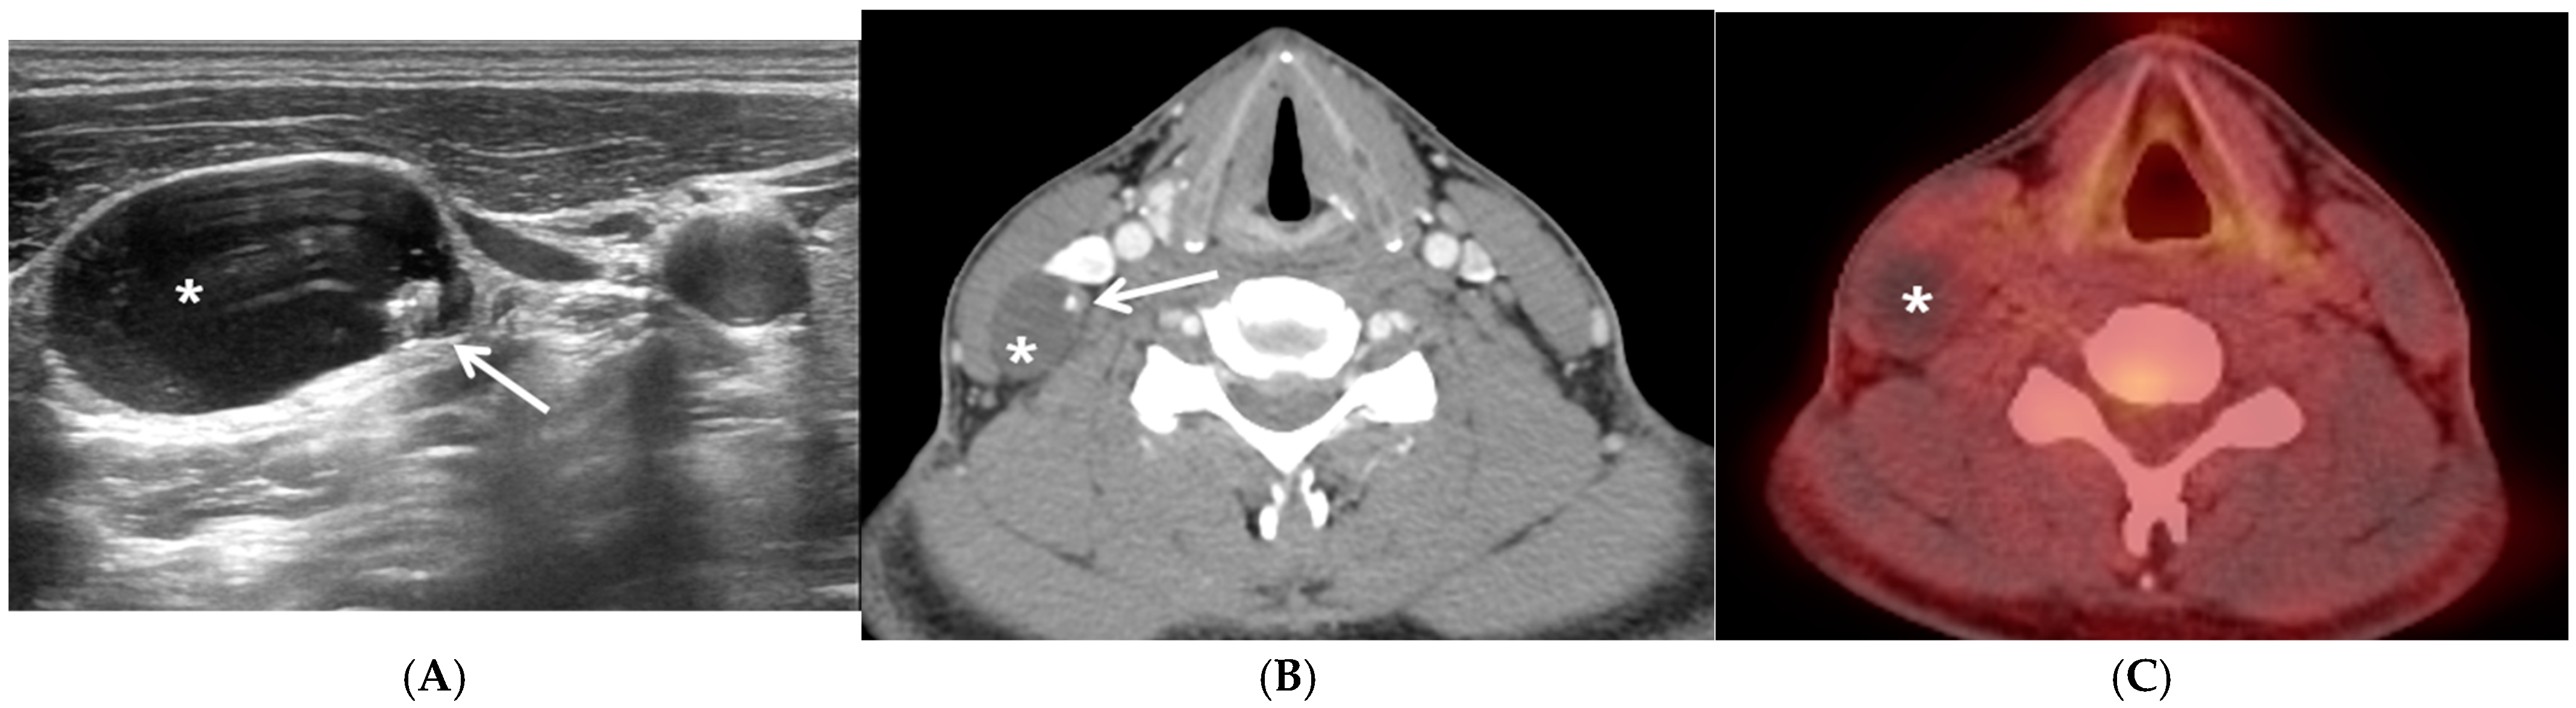

Thyroid Cancer Explore vol.3 no.2(2201 「Thyroid Cancer Expl Thyroid Cancer Treatment (PDQ®) - NCIの詳細情報

Thyroid Cancer Treatment (PDQ®) - NCI。Comparative Analysis of Metastatic Thyroid Carcinoma versus。The Role of Positron Emission Tomography/Computed Tomography。

Thyroid Cancer - Endotext - NCBI Bookshelf

Thyroid Cancer - Endotext - NCBI Bookshelf